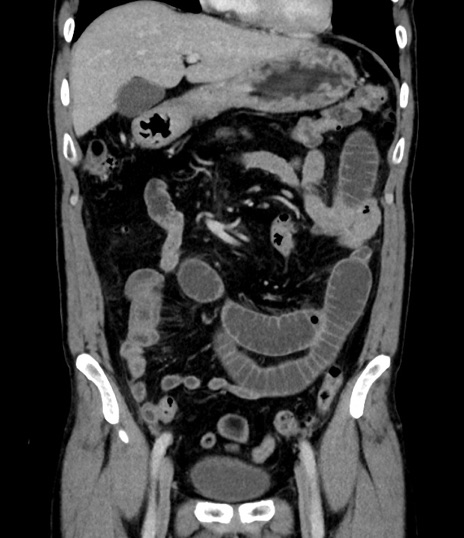

症例8(冠状断像)

【症例】 60歳代男性

【主訴】 黒色吐物

【現病歴】 4日前から嘔気自覚、2日前の朝食後にも嘔気あり、自分で手で嘔吐反射起こし嘔吐したところ血が混ざっていたため受診。

【既往歴】 5年前汎発性腹膜炎を伴う急性虫垂炎で手術、高血圧、前立腺肥大症、高脂血症

【身体所見】 腹部正中に手術癩痕あり 腹部平坦・軟圧痛なし膨満感あり

【データ】WBC 8400、CRP 4.54